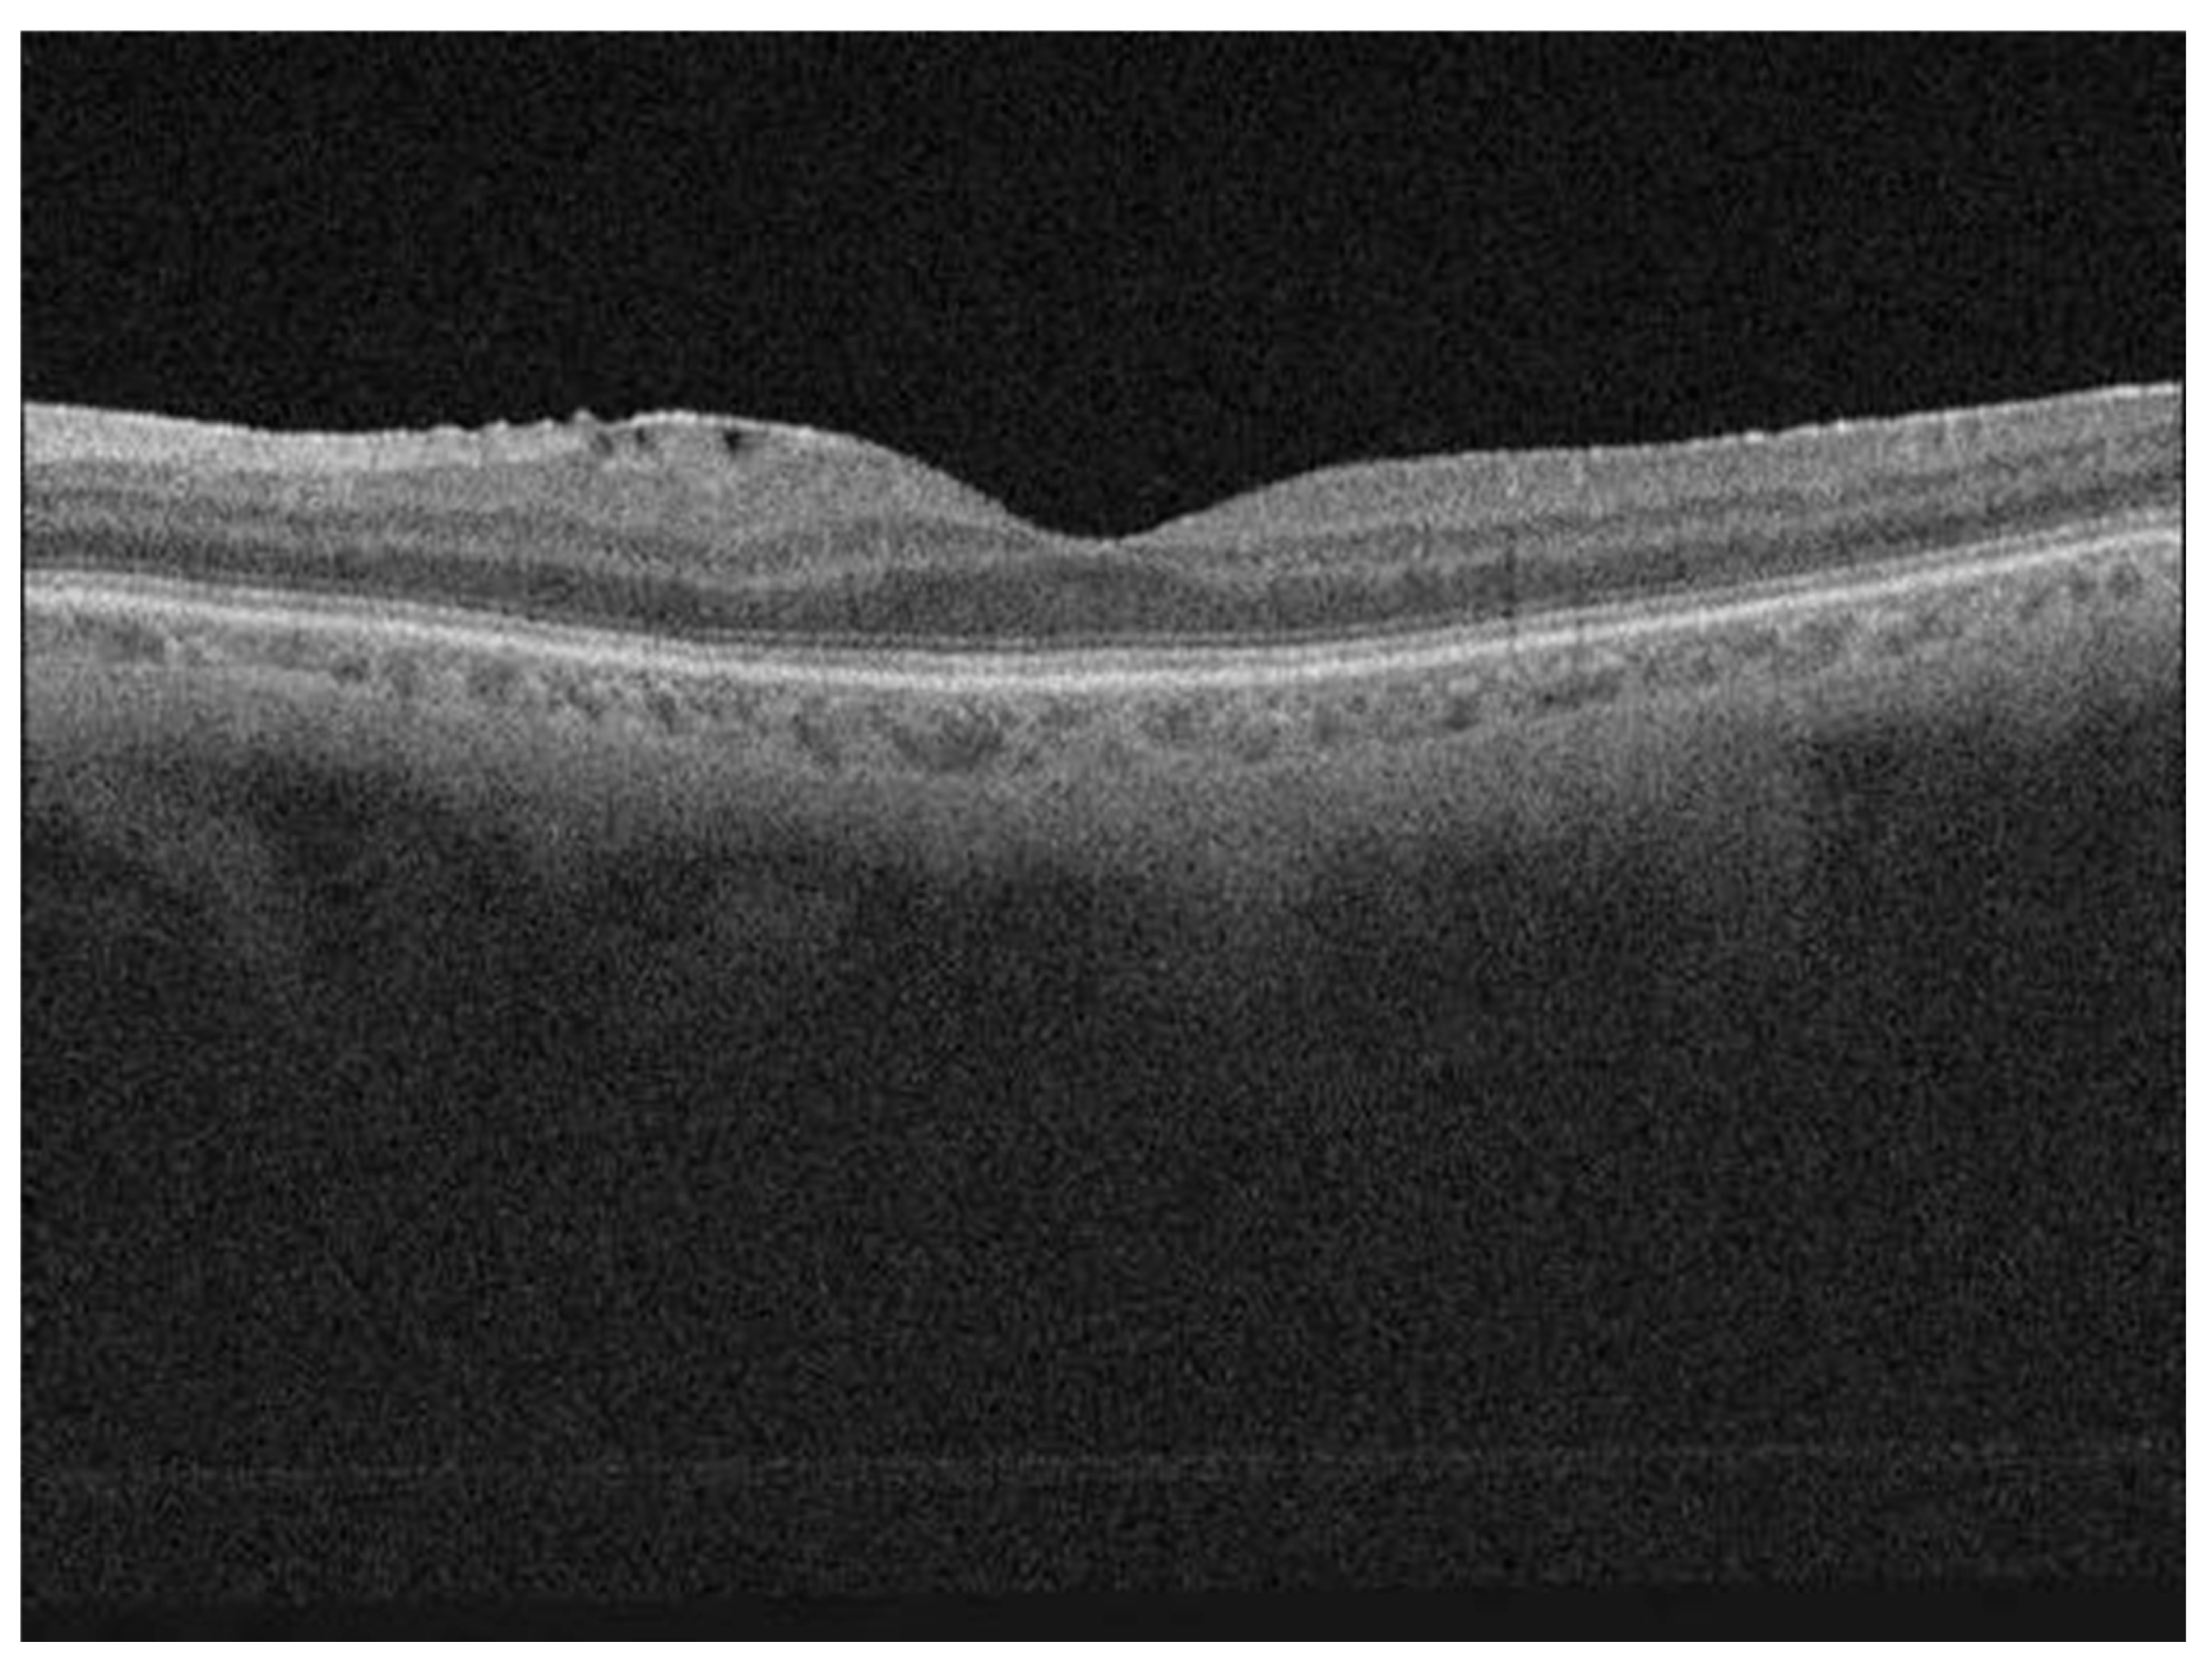

| OCT—discontinuity of ellipsoid zone | |

| No discontinuity | 54 (61%) |

| Discontinuity | 34 (39%) |

| OCT—status of EZ | −0.174 | 0.076 | 0.024 * | −0.325 to −0.024 |